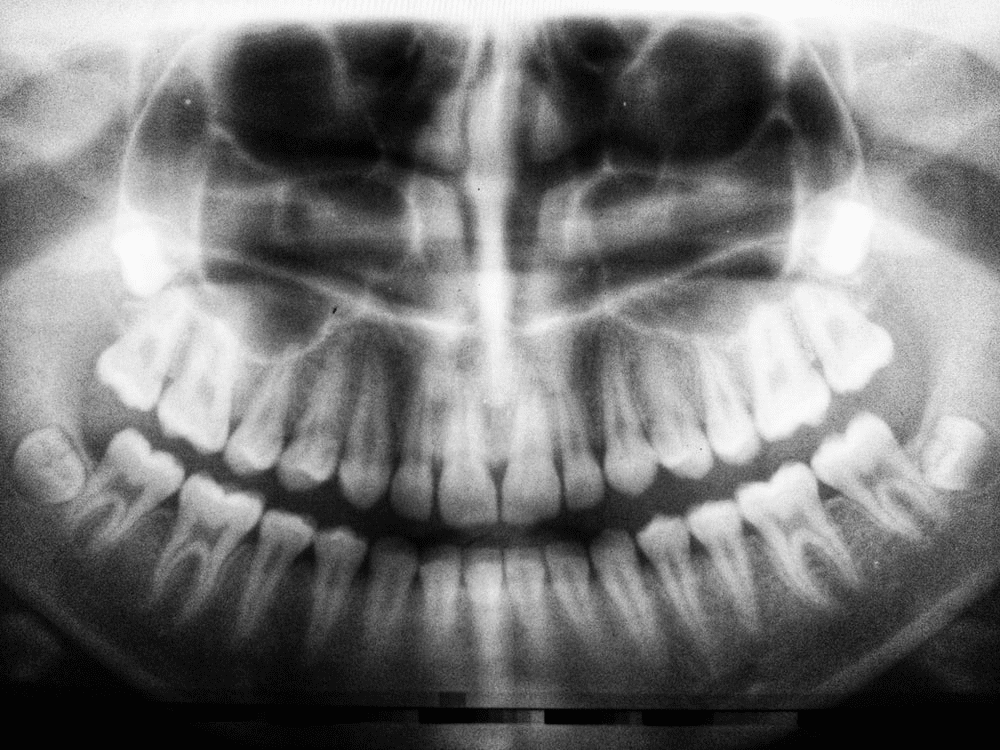

Have you noticed a cavity forming in your tooth but haven’t had the time to go get it checked out? Leaving it be will just worsen the decay level, and your natural tooth will be permanently affected. There are more than 15 million root canals getting performed every year, so if your dentist in Midland tells you …